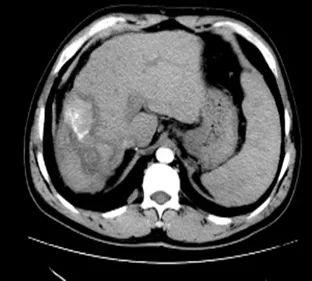

1. 肝脏原发病灶治疗前后磁共振扫描结果对比

淫羊藿素软胶囊治疗3、6、16、18个月后,肝脏病变呈现消融后改变,未观察到病灶进展。

治疗6个月

治疗16个月

治疗18个月